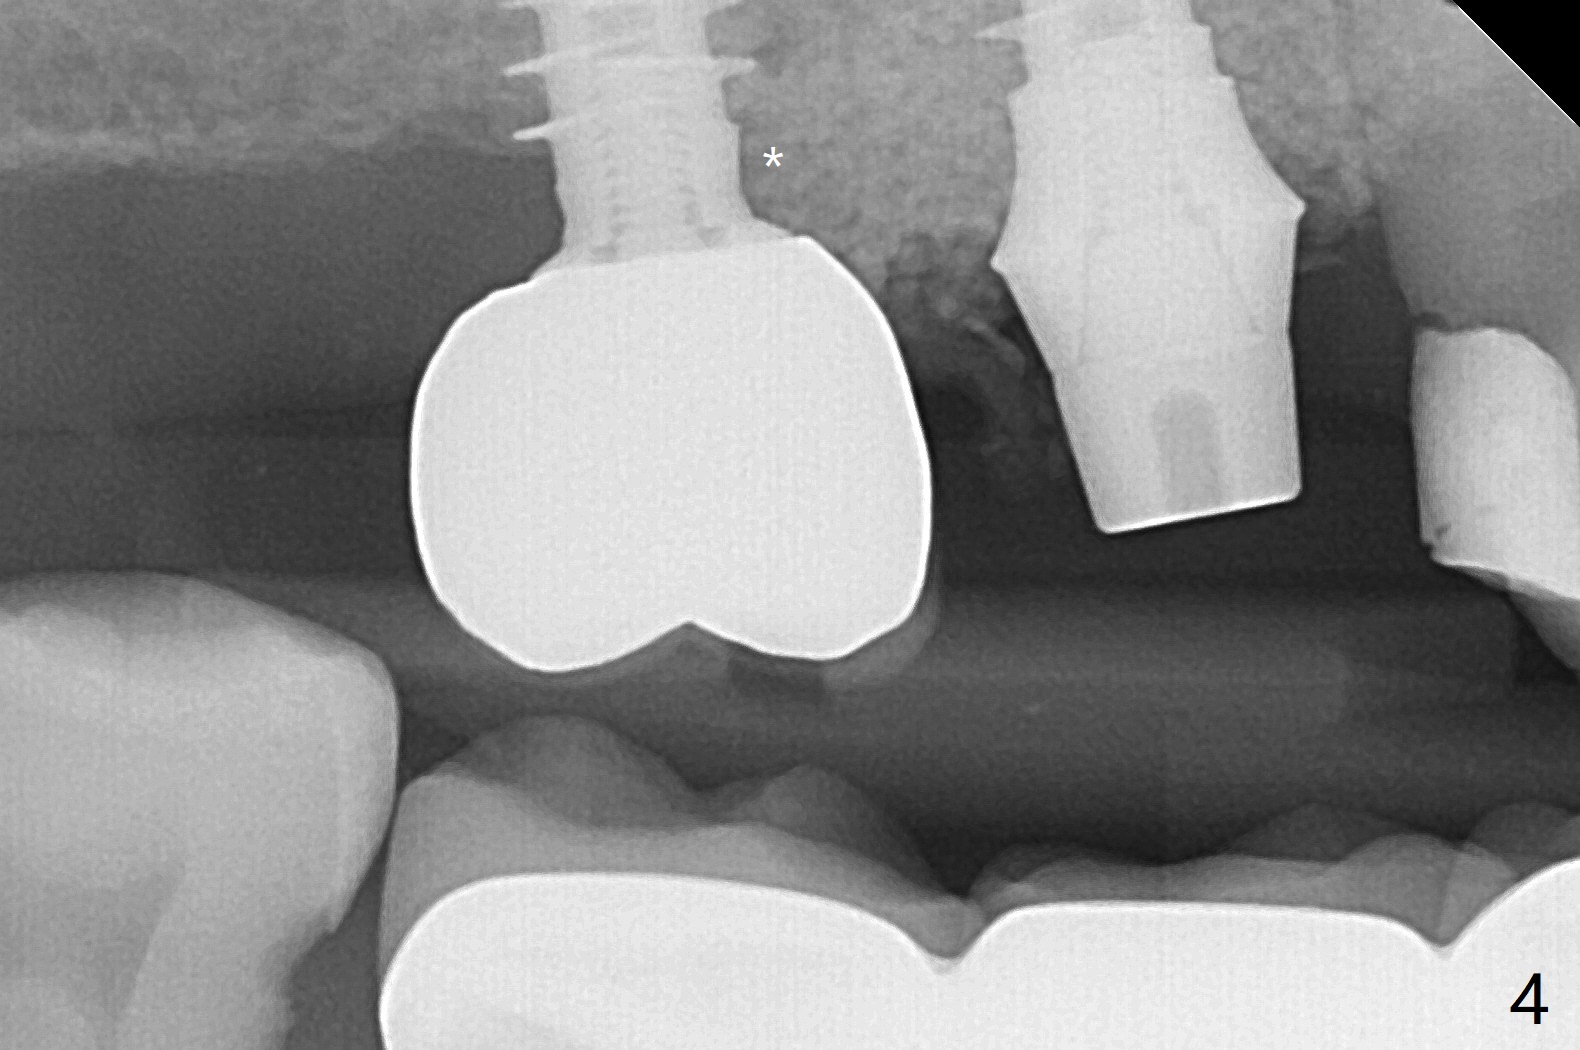

右上6拔牙困难,需要分根。3毫米补偿磨平钻头不能接触尖细中隔,即使使用外科手机和钻头,在导板指引下,尖钻头没有在中隔(S)打洞,使用2.2x7.3毫米钻头后,发现钻洞在近中颊侧窝。用过大一号钻头后,拍摄根尖片,方位偏差不大(图一,二),所以继续钻洞,钻头直径小0.5毫米,放置IS报废4.5乘10毫米植体,稳定性可以,也放置IS准基台(5.2x3毫米)。放置5x11(2)毫米Magicore(~20 Ncm),好像太接近近中牙槽骨(图三:*)。即刻放置4.3x3毫米实心基台。胶原塞放置远中颊侧和腭侧牙槽窝后,骨粉不仅覆盖刚植入的植体螺纹,而且推往7近中(图四:*(事先需要去除那里软组织,与图一比较))。其实可以先徒手用尖钻头在尖细中隔开始钻洞,为后来导板钻洞引导。